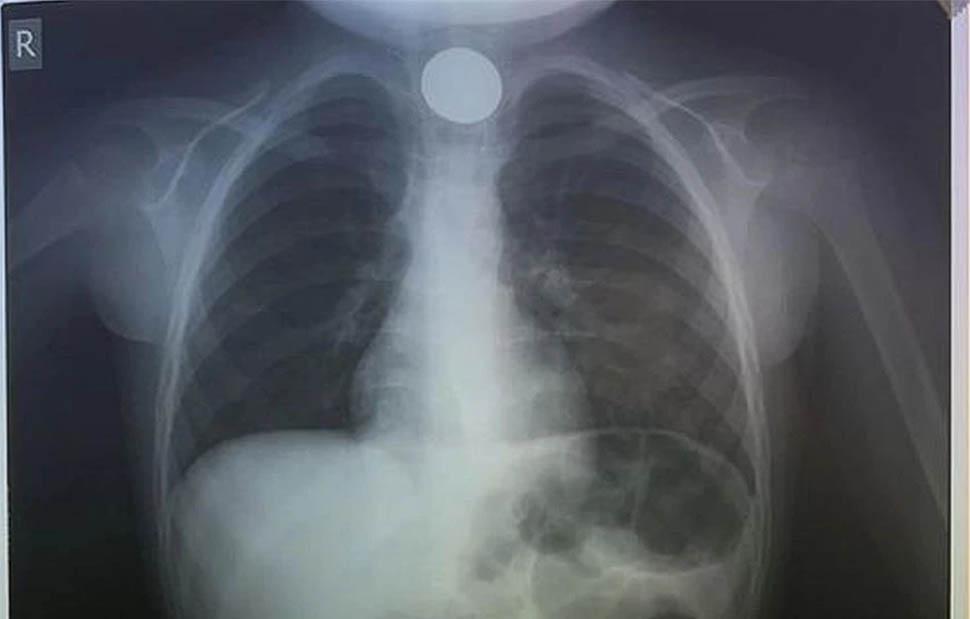

Η πρώτη κίνηση των γιατρών, ήταν να του κάνουν ακτινογραφία, για να δουν το σημείο που είχε σταθεί το νόμισμα.